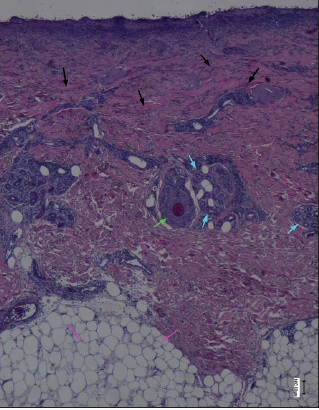

La realización de biopsias pre y postratamiento en 3 de los pacientes permitió observar 2 casos de desbridamiento parcial de la zona necrótica, siendo 1 caso una quemadura de tercer grado en dorso de mano que precisó de injerto (Fig. 25 a 34, caso 9), y el otro una quemadura previamente tratada con Flammazine Cerio® (Fig. 35 a 45, caso 12). En el tercero de los pacientes biopsiados apreciamos desbridamiento histológico completo de la zona necrótica con preservación de la dermis sana (Fig. 46 a 50, caso 11). Como hallazgos significativos, en las 3 muestras postratamiento evidenciamos un infiltrado inflamatorio linfocítico perivascular (Fig. 36, 40 y 48).

Uno de los aspectos más interesantes y novedosos de nuestro estudio son los hallazgos de los estudios histopatológicos. Una de las ventajas que parece tener Nexobrid® es la facilidad para el diagnóstico visual de la profundidad de la quemadura, que enlaza con la posibilidad de cubrir con injertos aquellas quemaduras que ya vemos que son de tercer grado, permitiendo un tratamiento conservador en aquellas zonas donde existe dermis viable. Nuestras 3 biopsias muestran una correlación del 100% con el diagnóstico clínico de profundidad de la quemadura tras el desbridamiento enzimático. Este diagnóstico no lo pudimos realizar antes de la aplicación del producto, ya que eran zonas de profundidad indeterminada, difíciles de valorar clínicamente antes del desbridamiento enzimático. Presentamos esta conclusión como uno de los puntos fuertes del tratamiento enzimático, ya que además de las implicaciones de la eliminación precoz de la escara, la facilidad de diagnóstico visual de la profundidad de la quemadura podría implicar un abordaje más fácil de las lesiones a la hora de decidir si injertar o si esperar a la epitelización espontánea.

Si bien planteamos la realización de las biopsias para comprobar la correlación clínico-histológica del diagnóstico de profundidad de la quemadura, evidenciamos una disparidad de criterio en la eficacia del desbridamiento según se considere el aspecto clínico o el histológico. Así, aunque nos pareció clínicamente que el desbridamiento fue completo en todos los casos, constatamos mediante la histología que no era así. Dos de las 3 muestras presentaron desbridamiento histológico incompleto. Sin embargo, 1 de ellas fue una quemadura de tercer grado que precisó injerto y en la que la reaplicación del producto no hubiese supuesto ninguna ventaja; en la otra, la quemadura epitelizó espontáneamente sin necesidad de mayor desbridamiento, por lo que nuevamente la reaplicación no parece que hubiese supuesto ventajas añadidas. De estos resultados podemos deducir que la valoración clínica de la eficacia del desbridamiento, aunque no coincide con la valoración histológica y tiende a sobreestimar la capacidad desbridante de Nexobrid®, sí parece suficiente para decidir la reaplicación del producto, sin precisar biopsias que determinen la eficacia del desbridamiento.

Otro hallazgo significativo de nuestro estudio es el incremento del infiltrado inflamatorio tras el tratamiento (Fig. 36, 40 y 48). Sin embargo, no podemos afirmar que sea consecuencia del tratamiento enzimático ya que no realizamos comparación con zonas de quemadura no sometidas a tratamiento con Nexobrid®. Además, en la literatura existe referencia al infiltrado neutrofílico típico que existe en la zona intermedia de la quemadura (región histológica comprendida entre la zona sana y la zona necrótica de la quemadura), pero el evidenciado en nuestro estudio es un infiltrado linfocítico perivascular que, hasta donde nosotros sabemos, no aparece mencionado en ningún estudio publicado sobre el desbridante Nexobrid®.(21) Aunque desconocemos si este infiltrado es originado o potenciado por el tratamiento con Nexobrid® o bien debido exclusivamente a la progresión de la quemadura, sería necesario estudiar si el posible incremento del infiltrado inflamatorio guarda correlación con la velocidad de curación o con el pronóstico a largo plazo, o bien es únicamente el resultado de la evolución fisiopatológica de la quemadura y no existen diferencias con el infiltrado evidenciado en las quemaduras no tratadas con Nexobrid®.

Estudio histopatológico en 3 pacientes: desbridamiento completo de la quemadura en 1 y parcial en 2, con abundante infiltrado inflamatorio linfocítico perivascular postratamiento. Los hallazgos histopatológicos se correlacionaron con la eficacia del desbridamiento valorado clínicamente en 1 de los 3 casos, y con el diagnóstico clínico de la quemadura en los 3 casos.